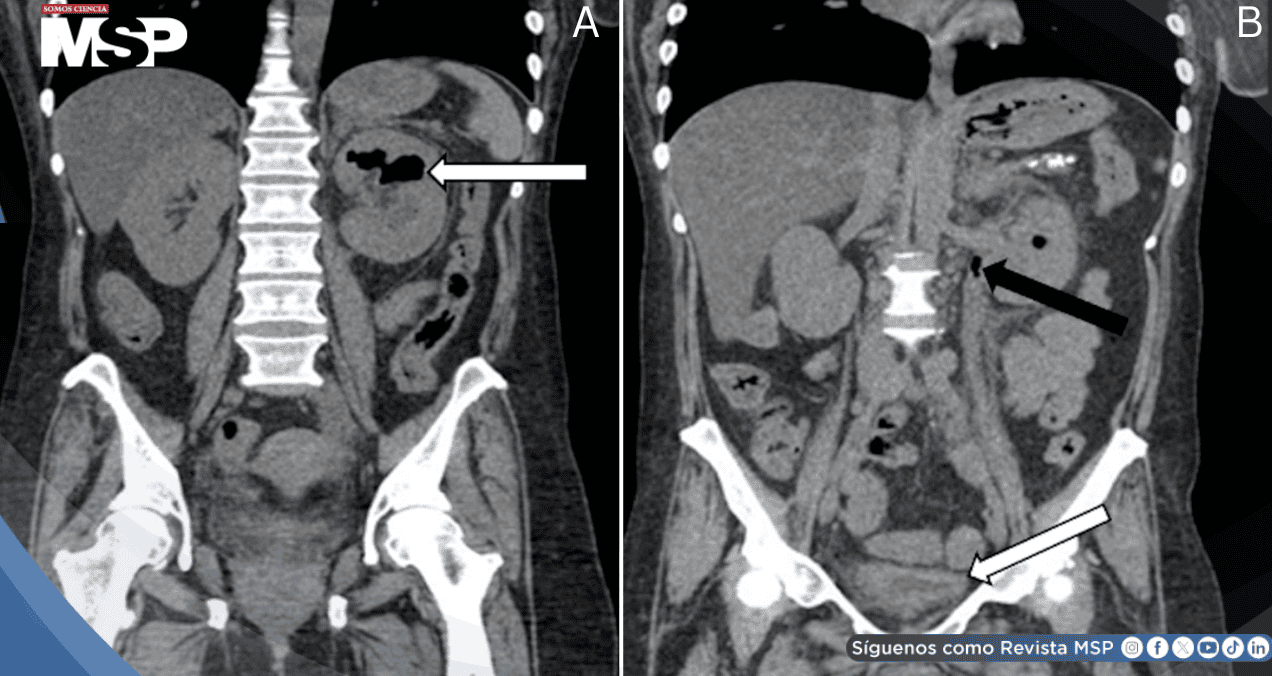

Durante la reevaluación, ante el deterioro clínico con taquicardia y dolor progresivo, se realizó tomografía computarizada de abdomen y pelvis sin contraste. Las imágenes demostraron hidronefrosis izquierda con presencia de gas en el sistema colector renal, hallazgo patognomónico de pielitis enfisematosa.

También se identificó hidrouréter, engrosamiento de la pared vesical y edema perivesical, sugiriendo propagación ascendente de la infección.